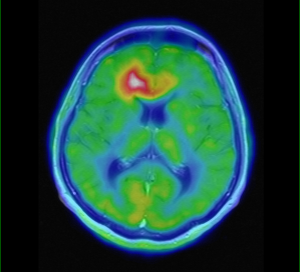

PET s 18F-FET

Diagnostika nádorov CNS